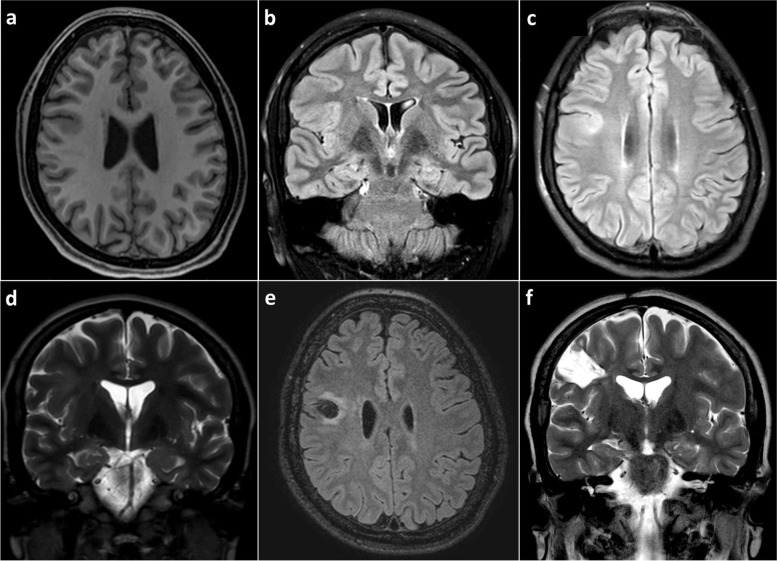

Case presentation: We report the case of a 21-year-old female with seizure onset at the age of 9, characterized by left-hand dystonic posturing and impaired awareness, which evolved to bilateral tonic-clonic seizures, evaluated in a neurological referral center in Lima, Peru. During 6-h video-EEG, interictal EEG revealing focal brief potentially ictal rhythmic discharges (BIRDs) over the right frontal central region, lasting less than 10 s. The ictal features were characterized by low-voltage fast activity over the same area. Brain magnetic resonance imaging (MRI) demonstrated a focal lesion of focal cortical dysplasia type II in the right frontal lobe. The patient underwent a lesionectomy guided by electrocorticography, which showed continuous polyspikes. BIRDs showing a brief burst of spikes lasting longer than 0.5 s, were also identified on intraoperative electrocorticography (ECoG) and helped define the extent of resection. The patient obtained an Engel Outcome Class IA at 6 years of follow-up.